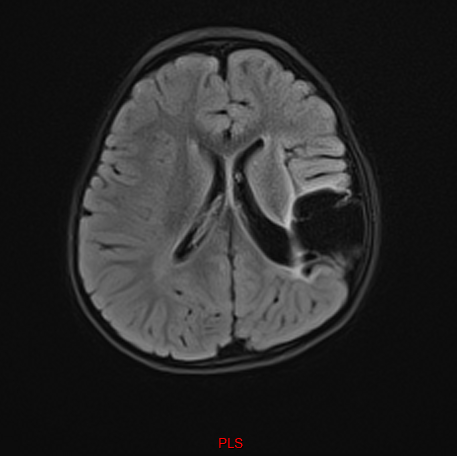

When the results came back, we were called into the consultant’s office. I remember her saying gently, “We did find something, but it’s important to focus on what Penny can do, not what the scan shows.”

Trying to lighten the moment, I joked, “So you found a brain then? No gaping holes?”

She smiled and said, “Hold that thought,” before turning the screen towards me.

And there it was — a huge, unmistakable void in her brain, a cyst filling the space where tissue should have been.

It felt unreal — like someone else’s life, someone else’s child. But also, it felt like I already knew. There wasn’t a big revelation; it simply confirmed what my heart had known all along.